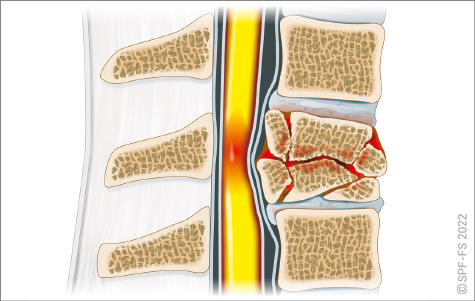

La colonne vertébrale

La colonne vertébrale, ou rachis, est un empilement de 33 ou 34 os articulés : les vertèbres. Elle supporte la tête et transmet le poids du corps jusqu'aux articulations des hanches. C'est sur la colonne vertébrale que sont fixées la partie arrière des côtes. Le rachis, qui contient et protège la moelle épinière, est traditionnellement divisé en cinq zones :

Figure 2-9 : la colonne vertébrale